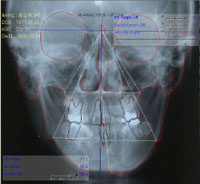

그림 3. 정모두부방사선사진의 투사도를 작성하고 분석을 시행한 결과 Me은 편위된 반면 ramus length의 좌우차이는 보이지 않아 기계적으로는 M type으로 판정되었다. 그렇다면 본 환자의 이부편위는 어떻게 나타났는가?어느 부위의 좌우차이가 본 환자의 이부편위에 기여하였는지 2차원적인 방사선사진만으로 잘 파악이 되지 않는다.

그림 6. 안면비대칭 진단을 위한 3-D Image Analysis 챠트와 환자 예. 안면비대칭 유무나 정도의 파악은 PA ceph으로 하고 안면비대칭 원인이나 양상의 이해를 위해 3차원 영상분석을 시행한다. 이부편위와 연관된 계측치를 좌우 구분하여 적고 이의 차이를 비교분석함으로써 안면비대칭을 정확히 이해할 수 있다. 본 환자의 경우 PA ceph에서는 이부편위 정도를 정량적으로 평가할 수 있는 반면 이의 원인을 이해하기는 매우 어려웠다. 실제로 PA ceph에서는 ramus height가 좌우 같게 나와 무엇이 이부편위를 야기하였는지 파악이 어려웠다. 그러나 3-D 분석을 시행한 결과 우측 ramus 길이가 좌측보다 길다는 것을 확인할 수 있었다. PA ceph에서 ramus height가 좌우 같게 나타난 것은 바로 frontal ramal inclination의 좌우 차이 때문이다. 본 환자의 이부편위는 우측 ramus와 body가 좌측에 비해 커서 (각각 7mm, 2mm 정도) 나타난 결과이기도 하지만 더욱 중요한 것은 frontal ramal inclination과 lateral ramal inclination이 우측에서 크기 때문에 이부편위가 더욱 심하게 나타났다는 것이다. 이부편위를 야기한 요소들을 조목조목 파악하는 것은 비대칭의 원인 이해 뿐 아니라 악교정수술 계획 수립 및 결과예측에도 큰 도움이 된다.